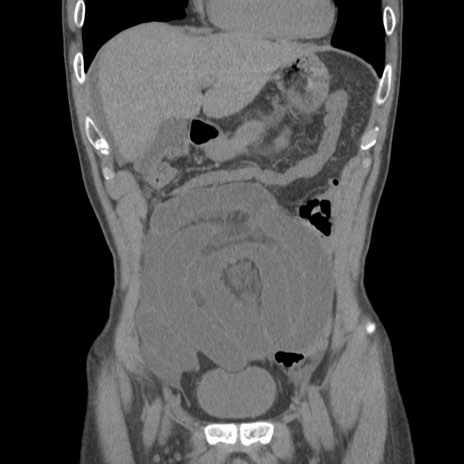

症例56 CT(冠状断像)

横断像